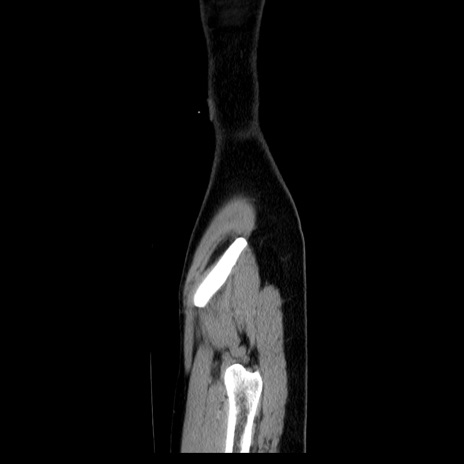

症例39(矢状断像)

CT